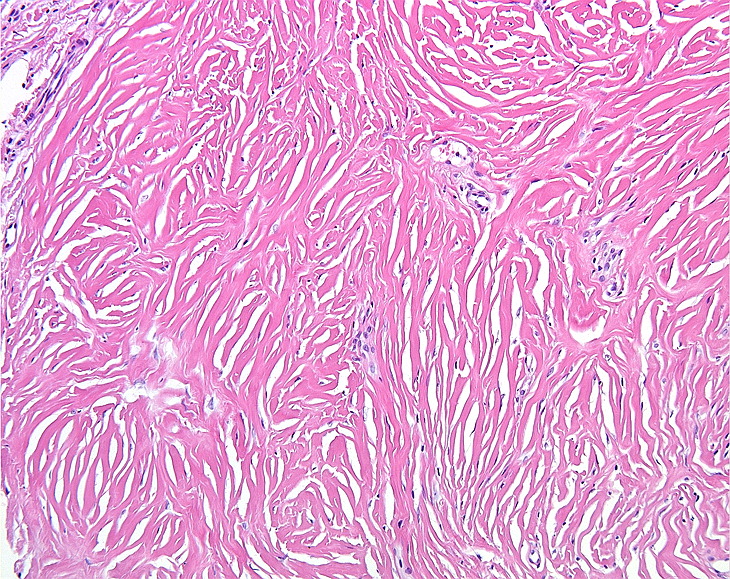

PA:Histologisch gaat het om bolvormige fibreuze tumoren

met een prominente vasculaire component, gelegen in de papillaire dermis. De

overliggende epidermis is atrofisch. Een haarfollikel kan aanwezig zijn in of

nabij de rand van de laesie. De oorspronkelijke naam trichodiscoma suggereert

dat de laesies uitgaan van de 'haardisk', maar daarover is twijfel. Daarom is

de naam discoid fibroma beter. Klinisch zijn het ook kleine ronde schijfvormige

Bij het Birt-Hogg-Dube syndroom wordt nu gedacht dat trichodiscoma en

fibrofolliculoma (en

perifolliculair fibroom) eigenlijk

dezelfde entiteiten zijn. En dat het afhangt van de plek en het moment van biopteren

in het beloop van de aandoening, en de richting van het aansnijden, welke diagnose

de patholoog er op stelt. De voorkeursterm is fibrofolliculoma. Het klassieke

fibrofolliculoma heeft centraal meestal een haarfollikel met een keratine plug,

omgeven door een mantel van mucoid of fibreus stroma. Ook kunnen er dunne strengetjes

van basaloid epitheel vanuit de centrale follikel lopen naar het omgevende fibrovasculaire

stroma, in een reticulair (netvormig) patroon. Deze epitheelstrengetjes en de

centrale haarfollikel worden niet gezien bij familiale multipele discoide fibromen.